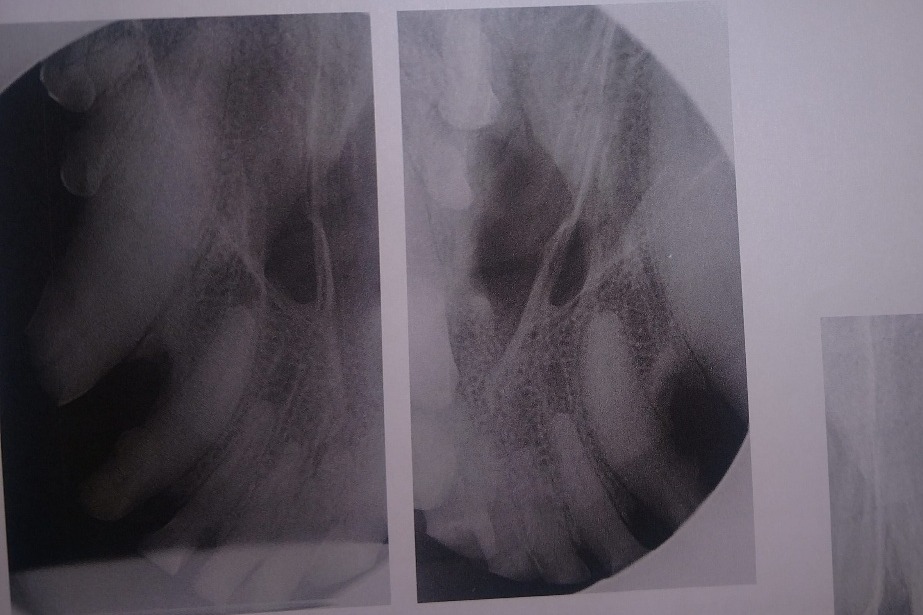

I had decisions to make. The surgeon could only work on 2 canines per day if I wanted to save them with root canals. Because 85% of jaw integrity rests on the roots of the lower canines, removing them would put her at a very increased risk to break her jaw in the future. With her having a clean mouth, she would be at a lower risk of infection following a dead and broken tooth into her jaw if I had just 2 root canals that day and waited on the rest of the work. Unfortunately, the broken canines (one upper and one lower) were on opposite sides, making them very difficult, if not impossible, to do the same day, as they would have to keep flipping her over at each step to get the opposite tooth.

So I chose the slightly worse broken canine (bottom left) and it's upper companion to get root canals that day. The upper right broken canine, in the photo above, would be much easier for me to see to monitor its condition while we saved up for more surgeries. That surgery, including the consultation, radiographs, and blood tests, came out to a total of $2,867.82.

The following photos are her radiographs for anyone that knows how to read them, so you can see all the dead teeth that need future extractions, and some show the root canals: